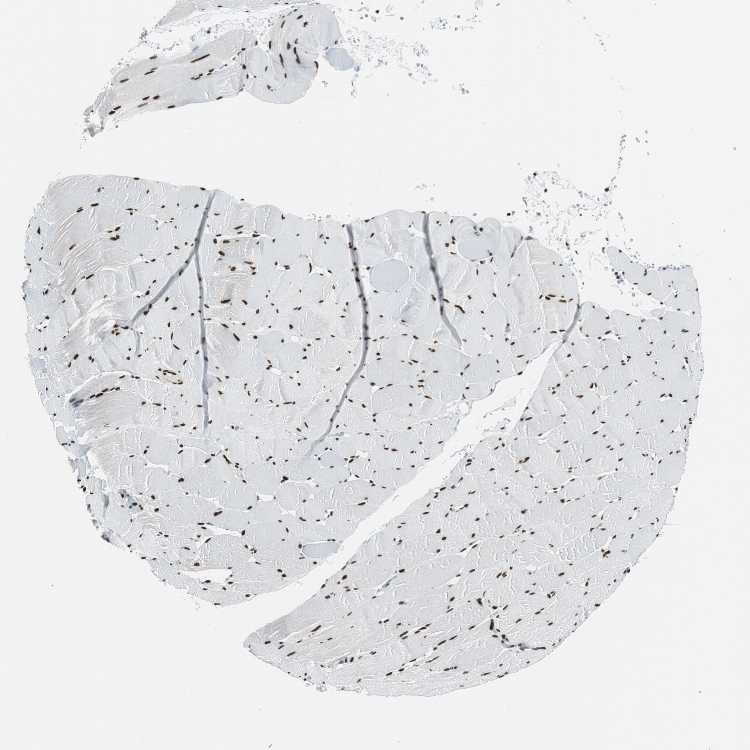

TISSUE PRIMARY DATA SKELETAL MUSCLE Show tissue menu

SKELETAL MUSCLE - Antibody stainingi

Antibody staining in the annotated cell types in the current human tissue is reported as not detected, low, medium, or high, based on conventional immunohistochemistry profiling in selected tissues. This score is based on the combination of the staining intensity and fraction of stained cells.

Each image is clickable and will lead to virtual microscopy that enables deeper exploration of all samples and also displays staining intensity scores, fraction scores and subcellular localization as well as patient and tissue information for each sample.

Antibody HPA051771Antibody HPA062953Antibody CAB004230

Myocytes HighMediumHigh